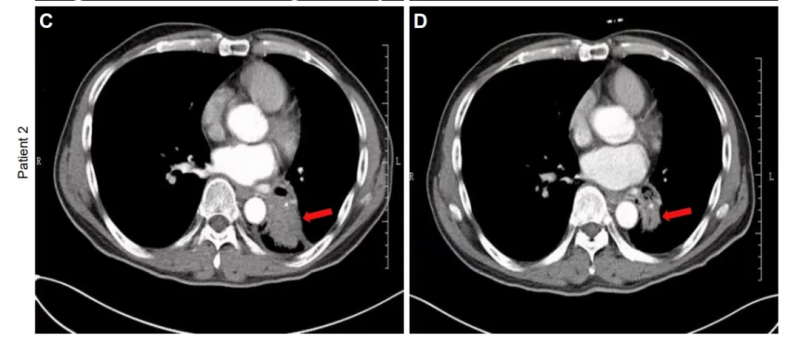

患者2:是一位57岁男性,患IVA期非小细胞肺癌(NSCLC),治疗前左肺下叶存在6.6×5.5×6.2cm肿块;治疗90天后肿瘤缩小至6.1×4.1×4.8cm(红色箭头示肿瘤位置)。

▲图源“JCI”,版权归原作者所有,如无意中侵犯了知识产权,请联系我们删除